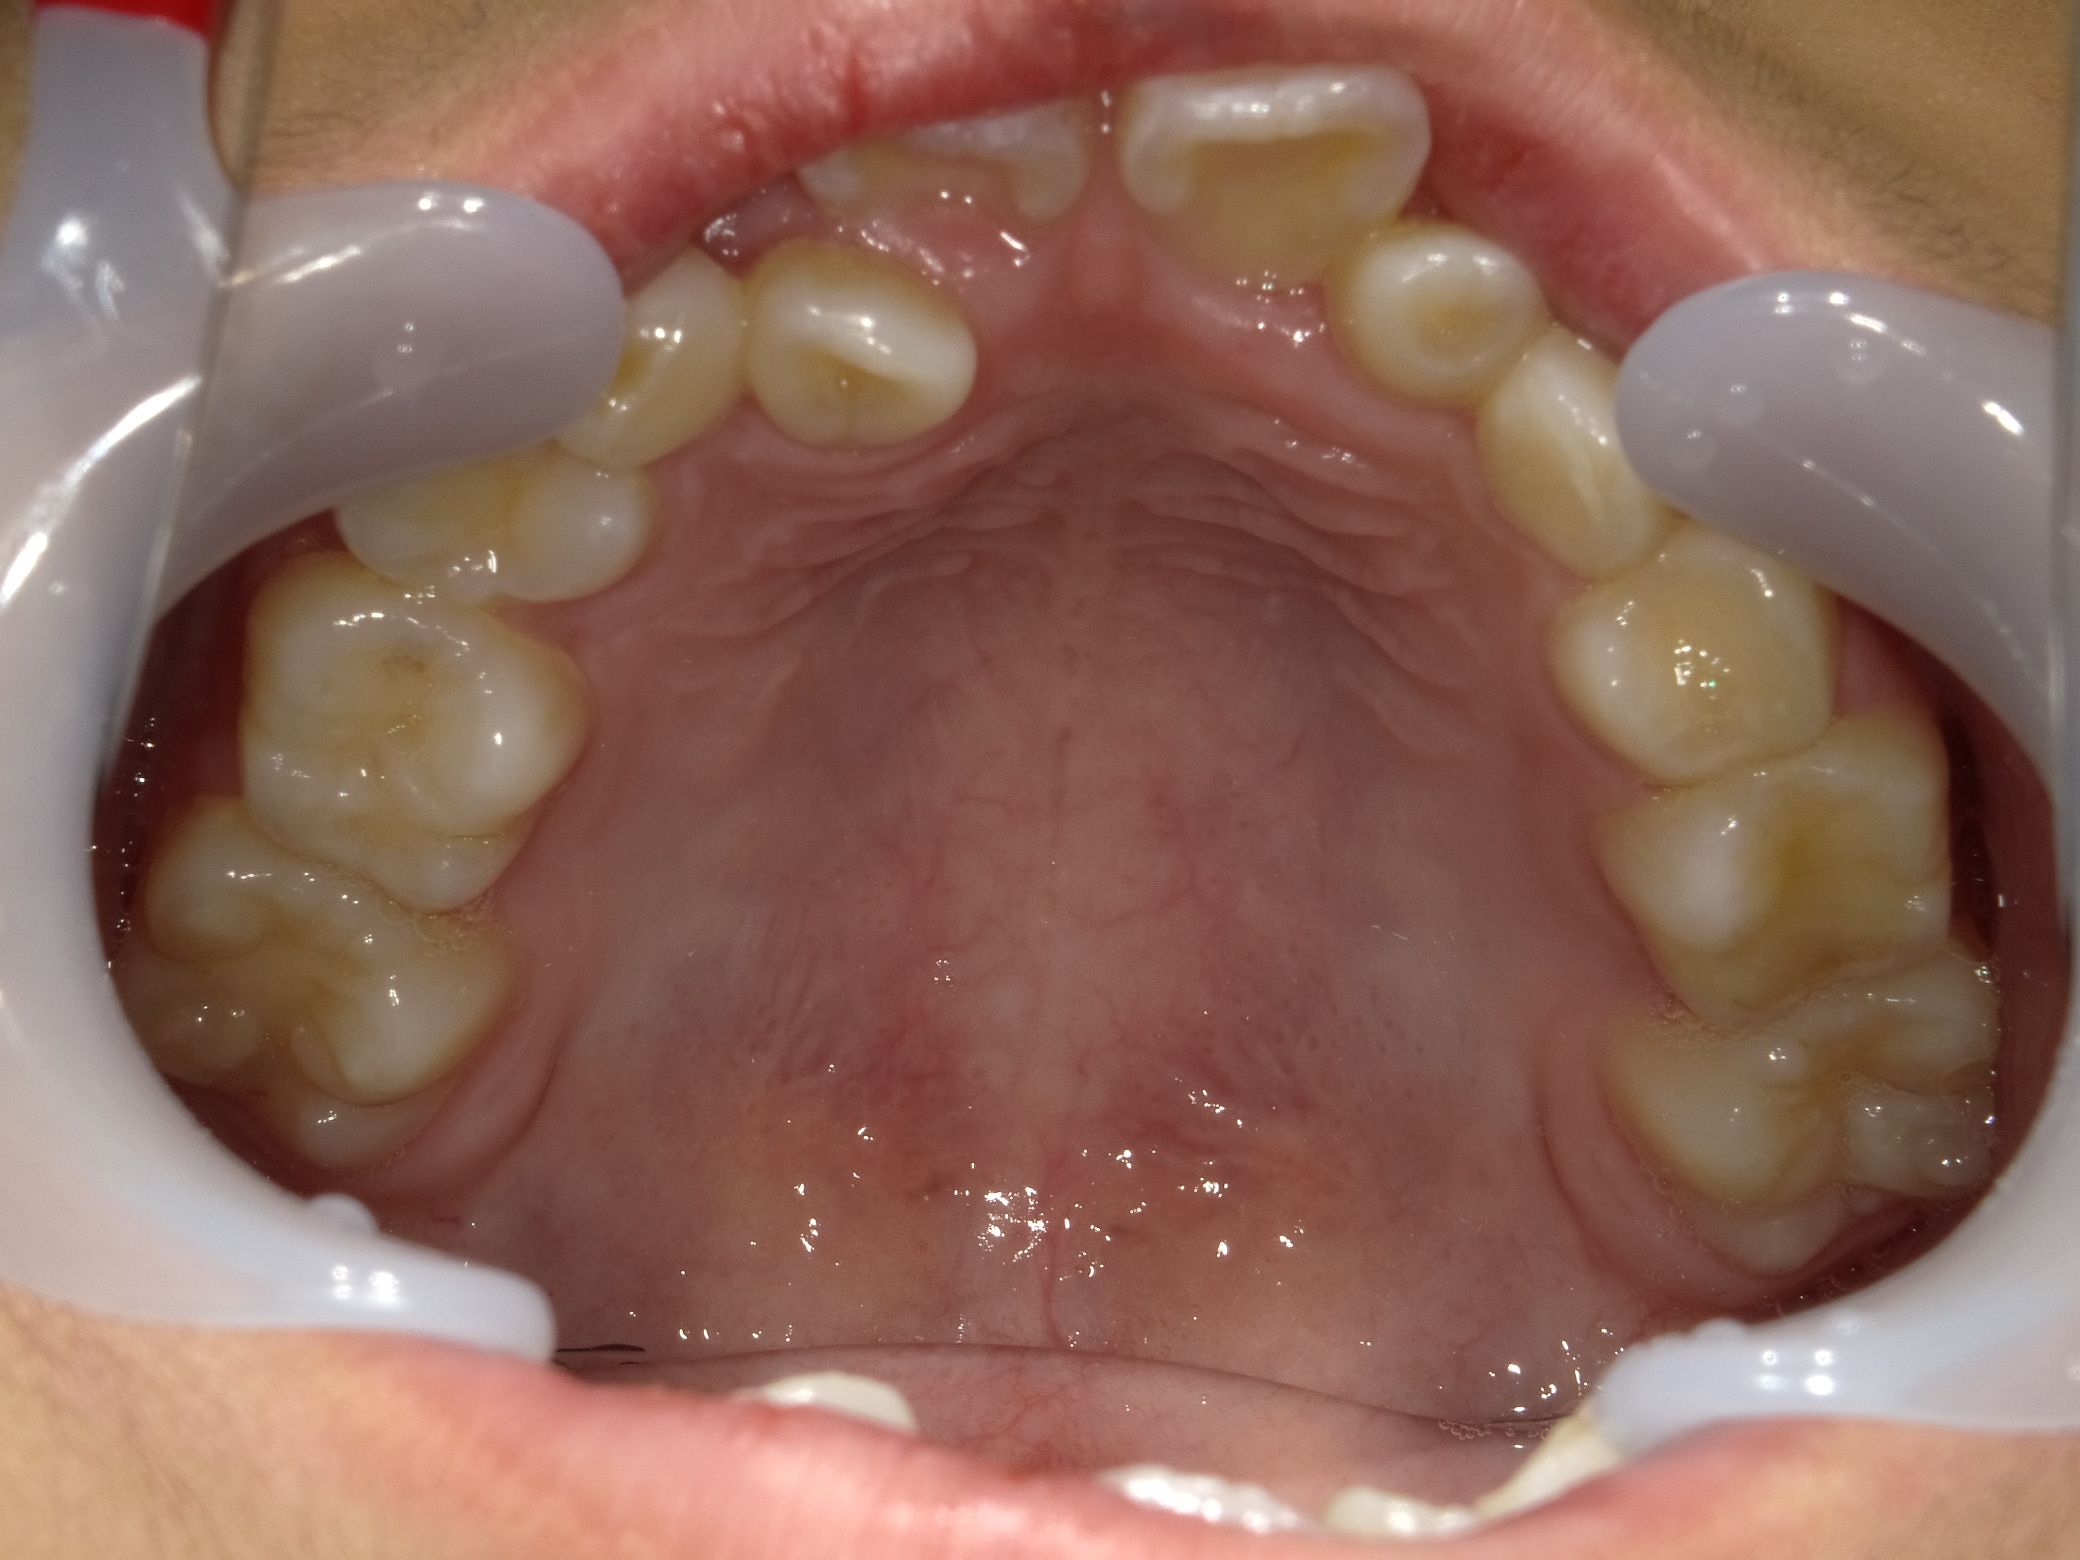

10代男性 叢生(歯のがたつき)・スペース不足・交叉咬合(一部分だけかみ合わせが反対)

治療内容:インビザライン・ファースト